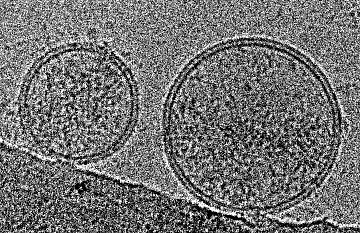

Fondée par Julie Hutin et Danièle Bensoussan, StemInow est une société biopharmaceutique pionnière dans les thérapies à base de cellules souches mésenchymateuses dans des pathologies inflammatoires et auto-immunes. Elle développe une plateforme de thérapie cellulaire innovante utilisant des cellules souches mésenchymateuses issues du cordon ombilical. Ces cellules possèdent des propriétés uniques – anti-inflammatoires, régénératives et antibactériennes – qui les rendent particulièrement prometteuses pour traiter les complications des pneumonies sévères évoluant vers un choc septique ou un syndrome de détresse respiratoire aigu.